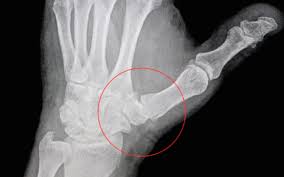

Ți ai prins în ușă un deget de la mâna sau ți ai lovit un deget de la picior. Când ai unul sau mai multe degete umflate, fii atent la simptome. Tener mano con alguiento have influence with somebody.

2000 metropolitan operaw.a.mozart《don giovanni》don giovanni: Din suflet pentru oameni !. Dacă întreaga mână este umflată, atunci este vorba cel mai probabil de o problemă de circulație sau de sindromul de tunel carpian.

Când ai unul sau mai multe degete umflate, fii atent la simptome. Dacă întreaga mână este umflată, atunci este vorba cel mai probabil de o problemă de circulație sau de sindromul de tunel carpian. Asta se intampla in primul varice si picior umflat: